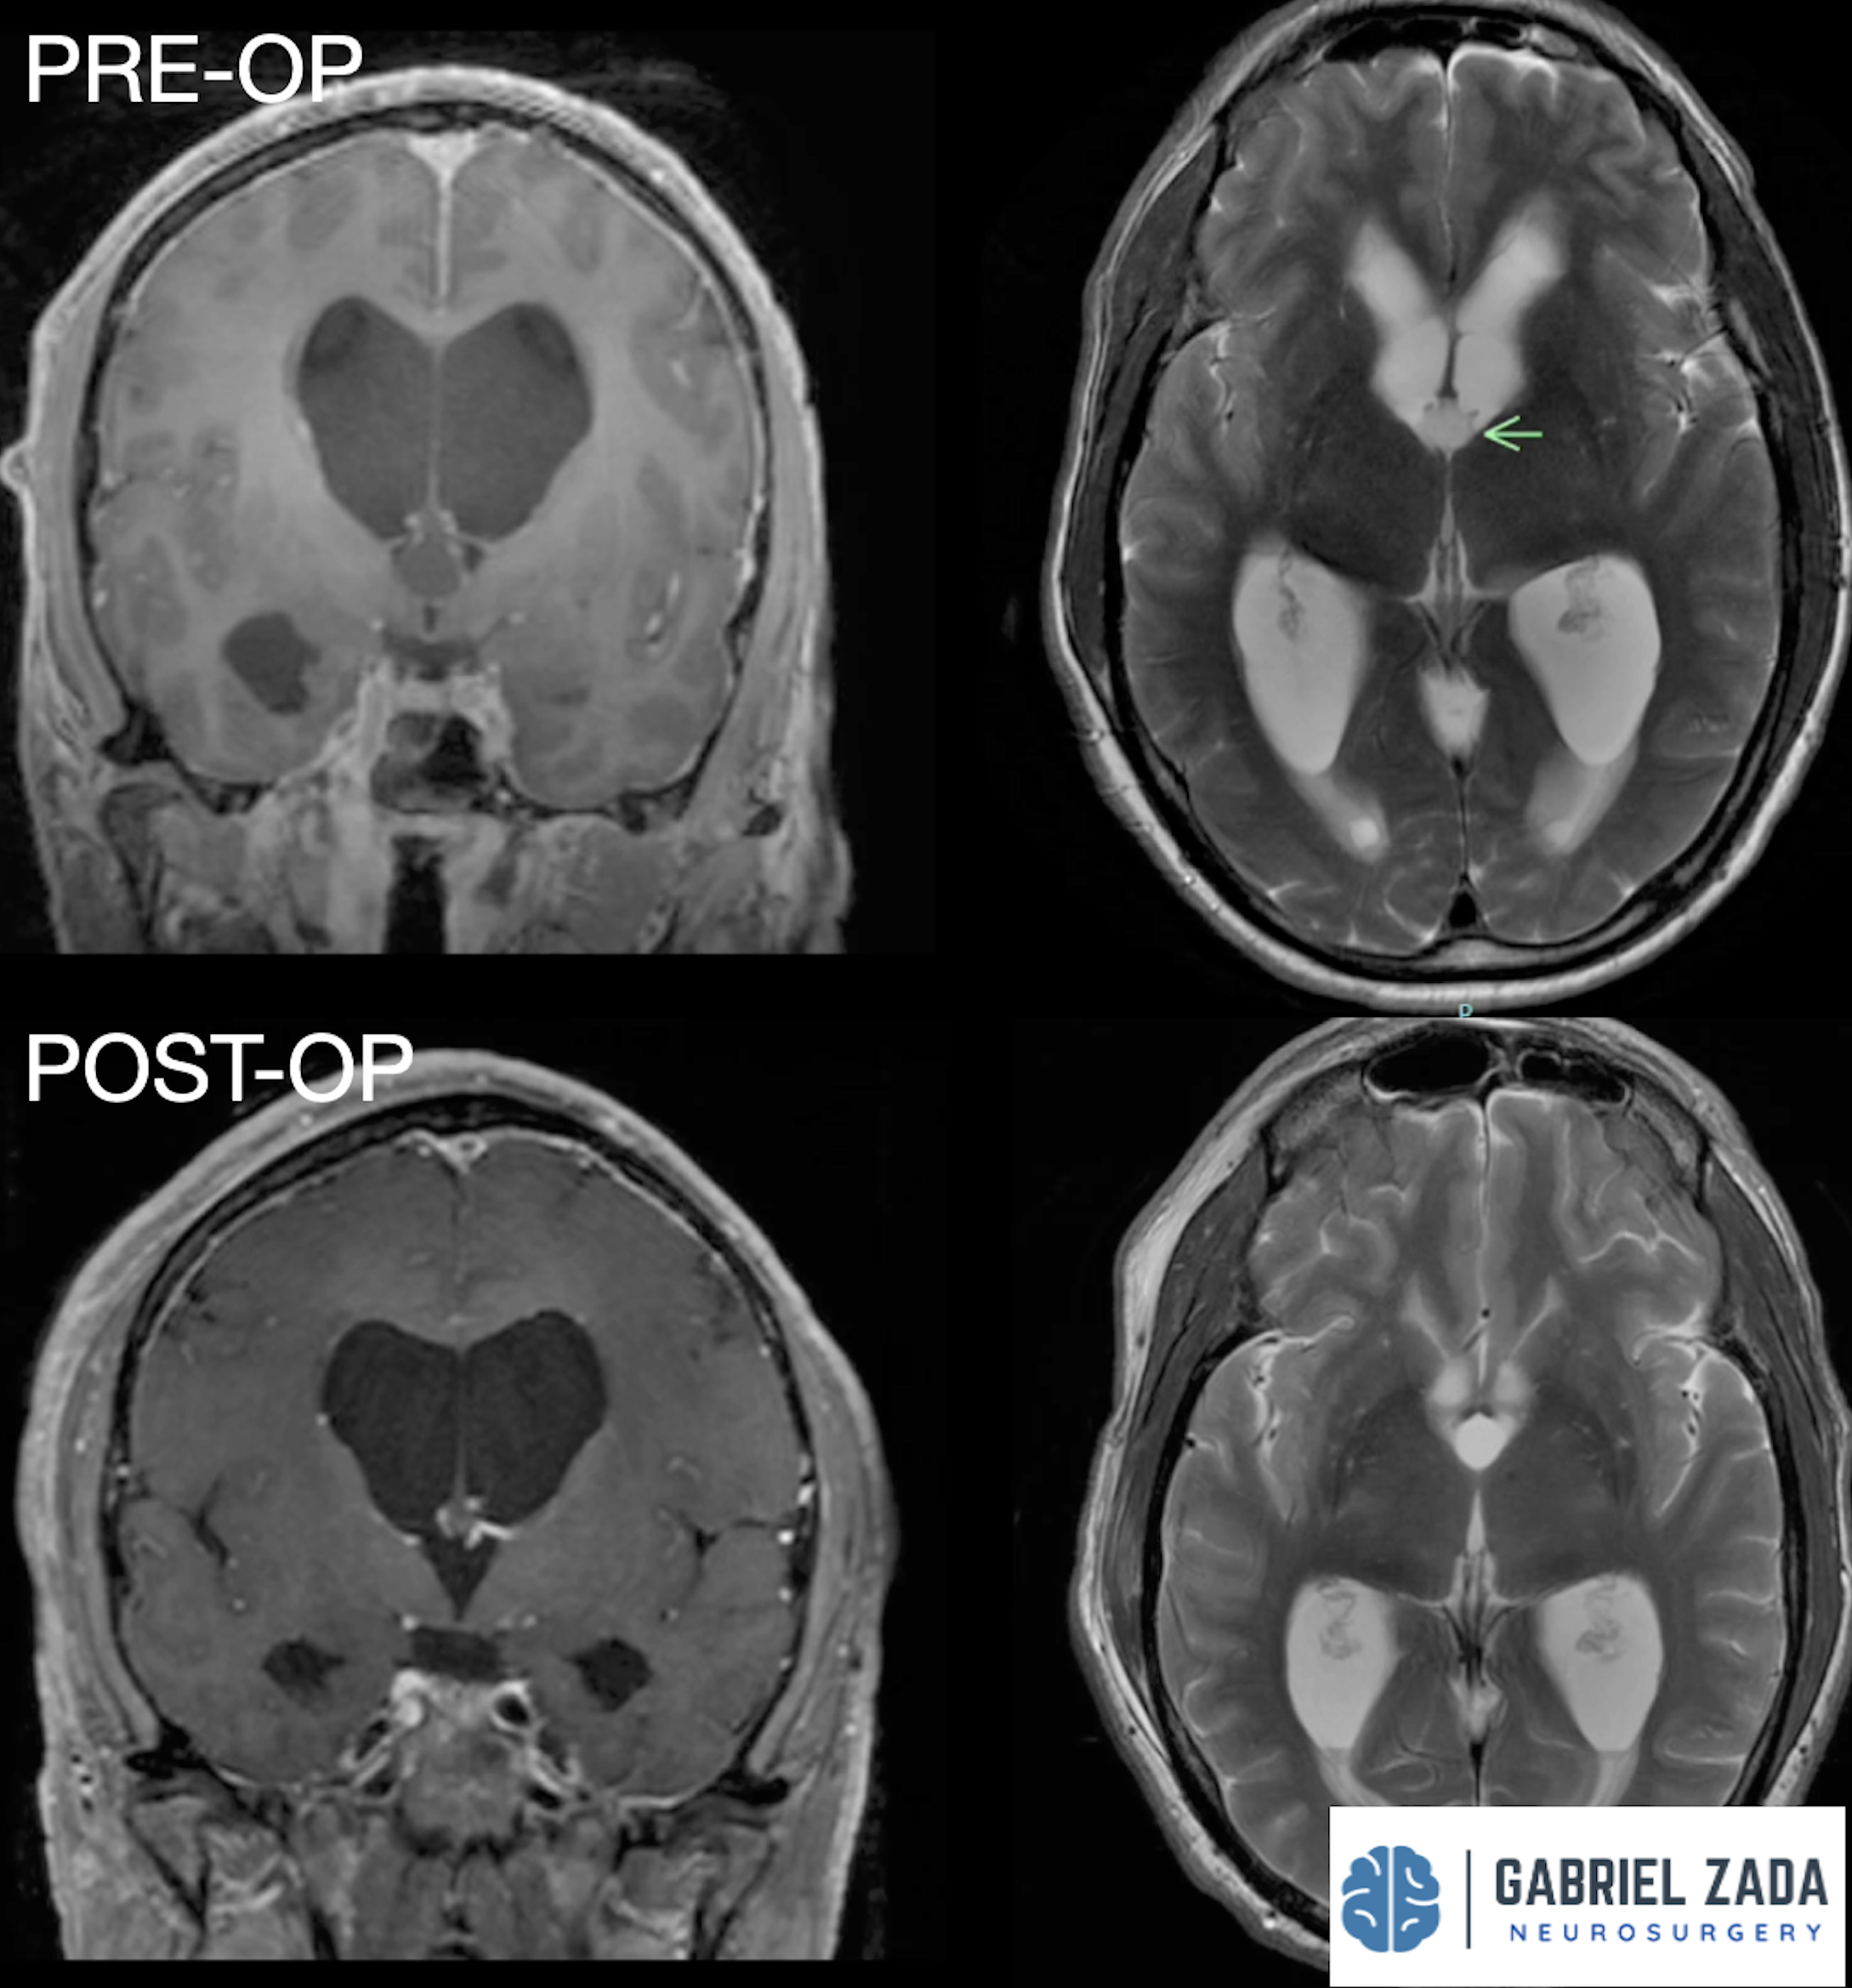

Explore this comprehensive gallery featuring pre‑ and post‑operative imaging of patients with skull‑base tumors treated by Gabriel Zada, MD, MS, FAANS, FACS. These cases highlight Dr. Zada’s expertise in advanced neurosurgical techniques and outcomes.

*Representative cases shown for educational purposes. All images de-identified. Individual results vary.